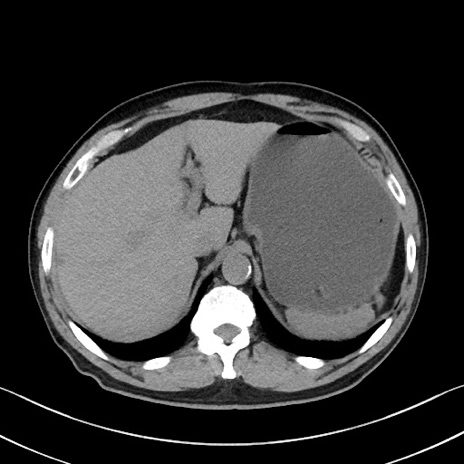

症例35(横断像)

【症例】70歳代 男性

【主訴】腹部膨満、嘔吐

【現病歴】昨日より腹部膨満感出現。本日増悪し、仙痛出現。嘔吐あり、受診。

【既往歴】糖尿病、胆摘後

【身体所見】BP 149/80mmHg、HR 74/min、BT 35.9℃、腹部:膨満、軟、圧痛なし。腸雑音減弱あり。上腹部正中切開瘢痕あり。

【データ】WBC 13500、CRP 1.72